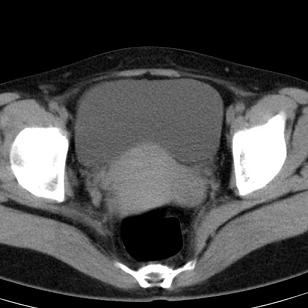

标题: CT19559:子宫及附件正常吗?

女,35岁,反复下腹部隐痛数月。

感觉上,子宫好象大了点

如果未孕,子宫体稍大,宫腔增宽,附件区未见异常密度影,还是建议结合b超检查为好,ct平扫对妇科没有优势。

子宫弥漫性等密度肿大,宫腔内缘见结节影突入腔内,子宫内膜异位可能